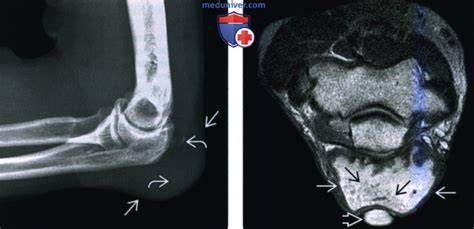

Локтевой сустав. Бурсит. | Портал радиологов

Рентгенограмма, МРТ, УЗИ при бурсите локтевого ...